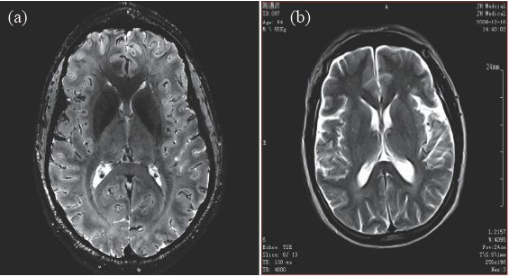

因此,磁共振成像技術目前的發展趨勢,是朝著更高磁場強度發展,以期獲得更高分辨率的圖像,并實現多核成像。圖6 顯示了磁場強度的高低對圖像分辨率的影像,(a)為7 T 磁場下的圖像,(b)為0.35 T磁場下的圖像,二者的圖像分辨率可見一斑。

圖6 T2 加權成像(a)7 T 下的成像,分辨率約0.3 mm;(b)0.35 T下的成像,分辨率約1 mm